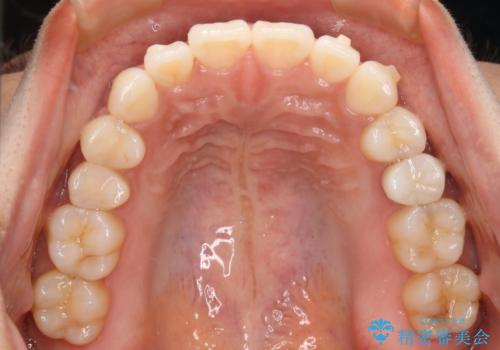

- インビザラインで全体矯正を進めてきましたが、装置の特性上右上2番目の歯の捻じれがなかなか治らず、シミュレーションを作り直すタイミングが来ました。

患者様と相談の上、短期間で確実な効果が得られるワイヤー部分矯正を取り入れて治療を進めることとしました。

丸みがあり掴みどころのない歯や大きい歯に挟まれた小さい歯は物理的にマウスピースの力が作用しにくく、作成したシミュレーションと実際の動きがズレることが良くあります。

こうした際に効率よく修正を行うには、歯に直接装置を張り付けて矯正力を伝えることのできるワイヤー装置を部分的に使うことが有効となります。

マウスピースはシミュレーションを作り直すことができるのが特徴ではありますが、苦手な動きは何度シミュレーションを作り直してもうまく動き切らないことも多いため、時間と費用を無駄にしないためにも思い切ってワイヤーへの切り替えを選択することも必要といえます。